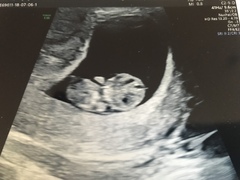

@hayleyfx So lovely, and how amazing that baby was moving, I can't wait to see that 😍

I'm sat here comparing my scans, only a week apart, and dwelling on the miracle that it is LIFE inside us ❤

@clairehr it's amazing how fast they develop isn't it?